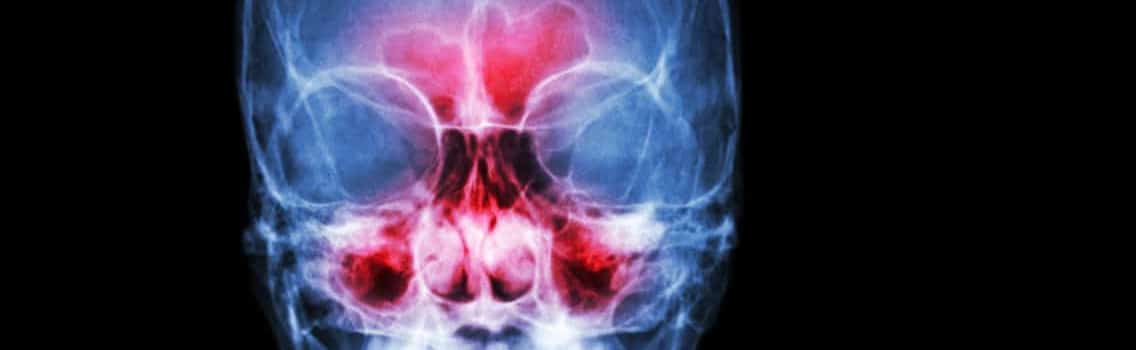

Sinusitis is a common condition where the tissues that line the sinuses become swollen and inflamed. This traps fluid inside and promotes germ growth, causing an infection. Many factors can cause sinusitis including nasal polyps, deviated septum, respiratory tract infections, allergies, foreign objects in the nose and additional medical conditions.

Chronic sinusitis results in a variety of cold-like conditions including congestion, runny nose, facial pain and pressure, loss of smell, fever, fatigue and dental pain. It is considered chronic when symptoms last eight weeks or longer.